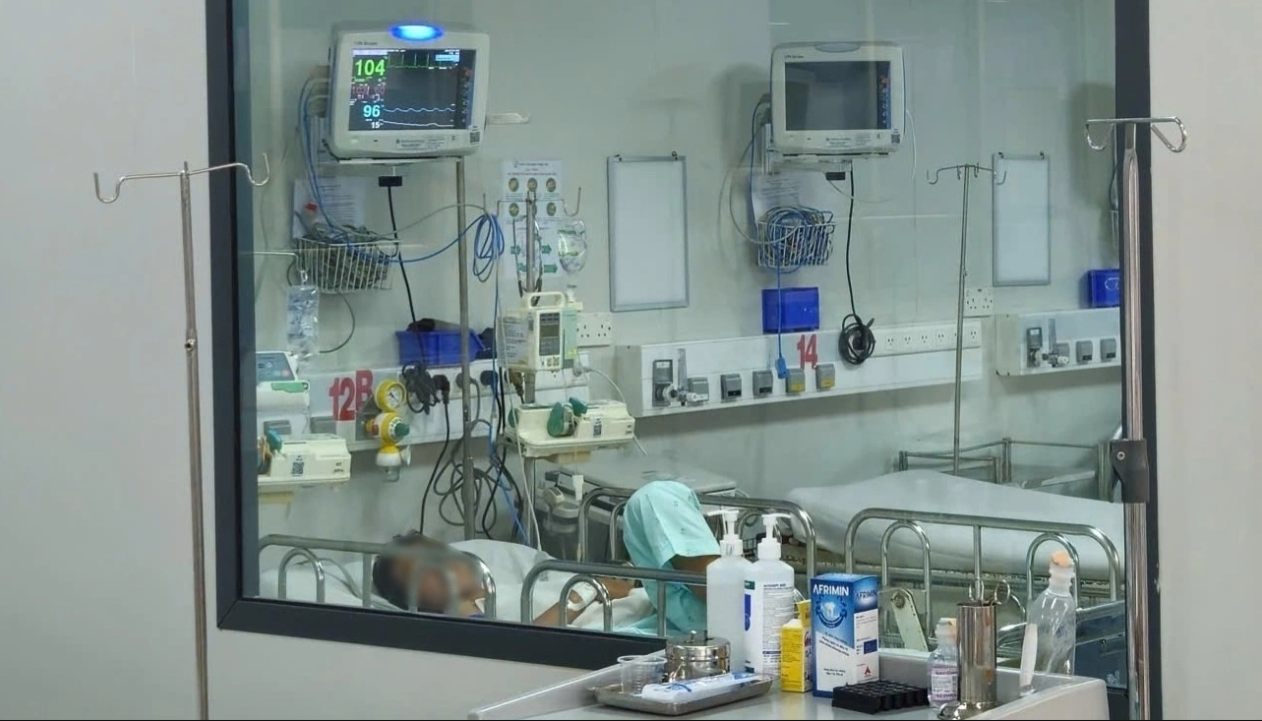

Nóng: Ghi nhận 1 ca tuvong do viêm não mô cầu, bé gái 11 tuổi ra đi chỉ sau một ngày phát bệnh

Theo báo cáo của Trung tâm Kiểm soát Bệnh tật TP.HCM (HCDC), qua điều tra dịch tễ tuần 14 (30/3-5/4), thành phố ghi nhận một trường hợp tại phường Hòa Hưng mắc viêm màng não mô cầu không qua khỏi. Kết quả cấy dịch não tủy xác định dương tính với vi khuẩn Neisseria meningitidis, nhóm huyết […]